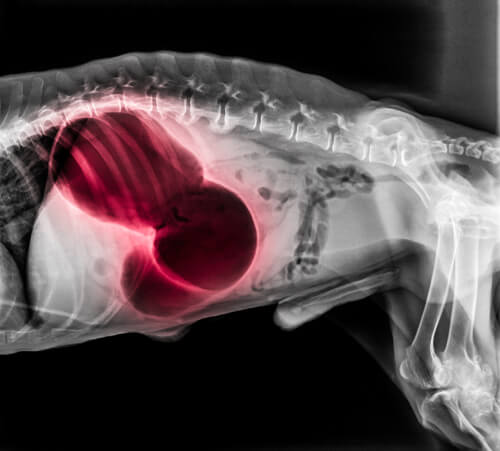

En caso de suceder en el área del corazón o los pulmones

En estas zonas, un coágulo puede conducir a una variedad de síntomas sistémicos de mucha gravedad. Entre ellos puede presentarse desmayo, falta de aliento y parálisis. Pueden ocurrir encías pálidas o azules, incapacidad para dormir o tos con sangre. El tromboembolismo pulmonar suele ser mortal.